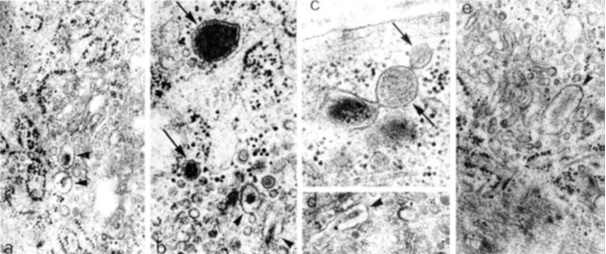

Фигура 4. Електронно-микроскопски микрографии на секреторен фенотип васкуларни гладкомускулни клетки на експериментални животни. a-e. Посочени са секретопни вакуоли със сферична(стрелки) и елонгирана (глави на стрелки) форма. x 20 000. От: (8).

Фигура 5. Електронно-микроскопски микрографии на секреторен фенотип васкуларни гладкомускулни клетки на експериментални животни. a. Асоциирани с комплекса на Голджи клатрин-облечени везикули (стрелки). b. Елонгирана вакуола, свързана с микротубул чрез къси филаментозни структури (две стрелки). c. Произхождащ от плазмалемата клатрин-облечен везикул (три стрелки). d. Група от Голджиеви везикули, разположени между микротубули. e. Микротубули, асоциирани с гранулиран ендоплазматичен ретикулум. a, c, d x 50 000; b x 80 000; e x 20 000. От: (8).